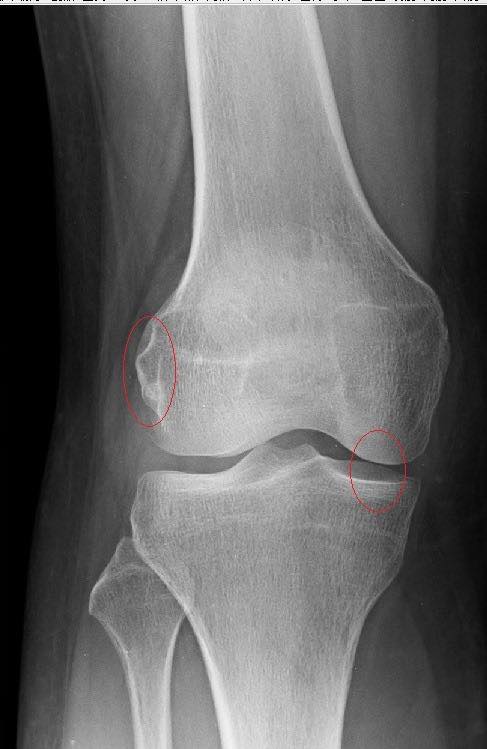

很難想像年輕的呂小姐膝蓋持續疼痛超過十年,當初座車大約二十分鐘後突然膝蓋刺痛,完全站不起來,開始慢性疼痛,幾個月後開始連上廁所也完全蹲不下去,上述症狀持續快一年,激烈運動或走路超過一個小時就會痛,久坐也會誘發疼痛,在台北某診所打過五次PRP效果也不好,觸診發現內側皺壁壓痛明顯,髕下脂肪墊壓痛,懷疑退化性關節炎第二期,原本要去嘉義大林找權威醫師開刀,但呂小姐的媽媽曾經動過該知名手術,術後疼痛復原時間長達半年以上,以她上班族的病假無法負荷,而且需要半年都拿拐杖也不是辦法.這次經友人介紹來接受膝關節整合中醫微創療法

診斷:退化性關節炎第二期

髕下脂肪墊受傷

內測皺壁摩擦綜合症候群

✅第四期的患者,關節軟骨耗損嚴重,從X光清楚看到完全沒空隙且關節嚴重變形,還是建議找骨科醫師開刀為主